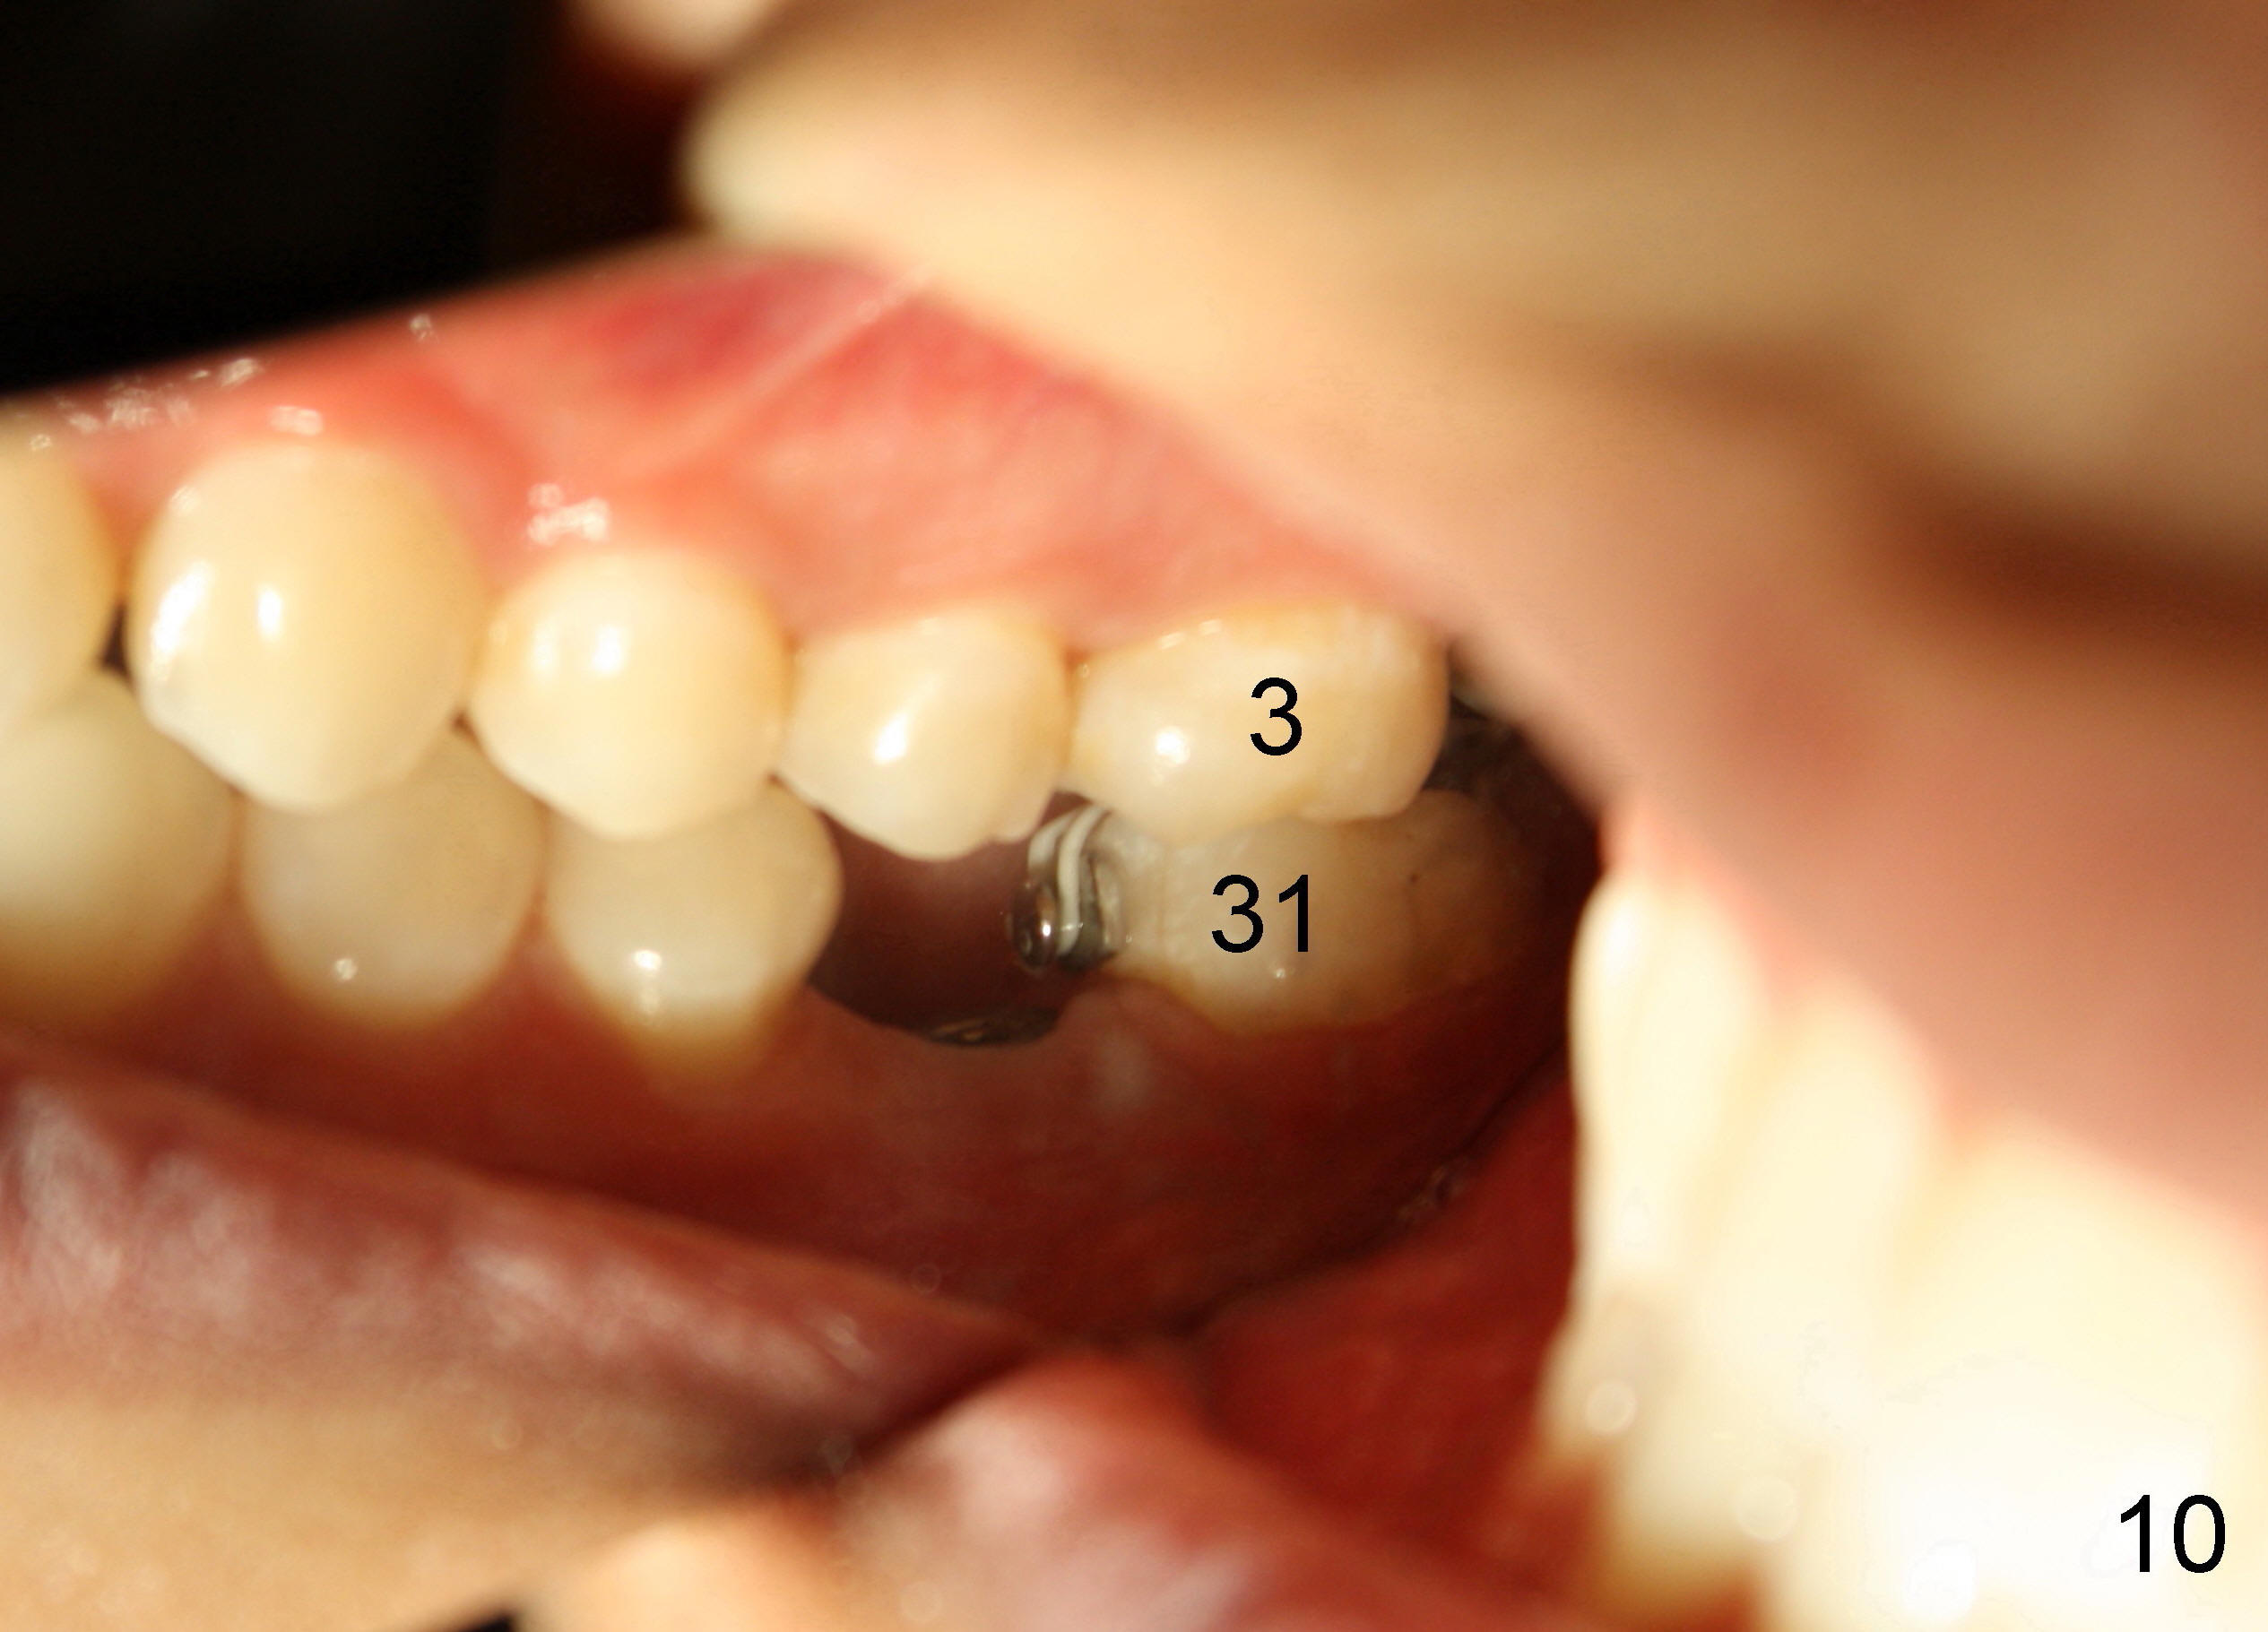

The tooth #31 is uprighted in six months (Fig.8, as compared to Fig.5). The edentulous space increases from 6 mm to 9 mm mesiodistally, which is still not enough. The M-D width of #19 is 12 mm. In fact, the tooth #2 has been intruded substantially (Fig.9. Compare to Fig.3). The possible reason for resistance of distal movement of #31 is an interference from the tooth #3 (Fig.10). A regular implant is placed intentionally in the distal aspect of the edentulous area (Fig.11: I). The next plan is to place temporary crown on the implant once it osteointegrates to raise the occlusion efficiently so that the tooth #31 is free to move distally with retraction of power chain attached to the mini-implant (as shown in Fig.2). The regular implant may be also used as anchorage to push #31 distally. See you later.